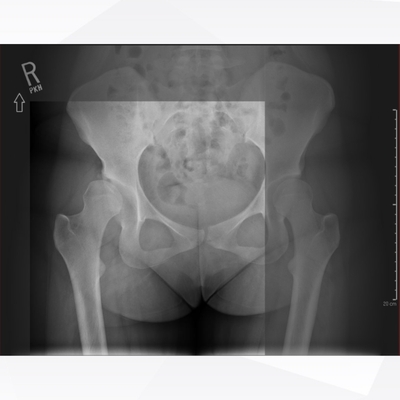

Click on an image below to view more info.